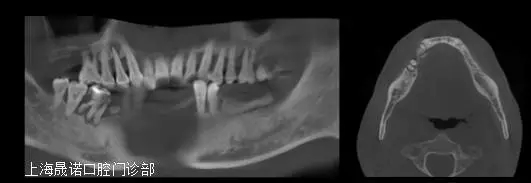

術(shù)前影像檢查分析

640.webp (2).jpg

雙側(cè)后牙區(qū)唇側(cè)不規(guī)則骨缺損,最大骨寬度為7mm,高度尚可。CBCT掃描顯示下頜余留牙牙周支持組織重度喪失和伴根尖周病變、繼發(fā)齲。